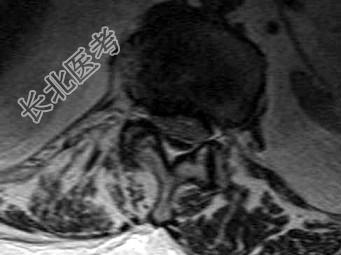

- 单项选择题男,59岁, 硬膜外麻醉后背痛1周余,结合MRI检查, 最可能的诊断是 ( )

E、硬膜外血肿